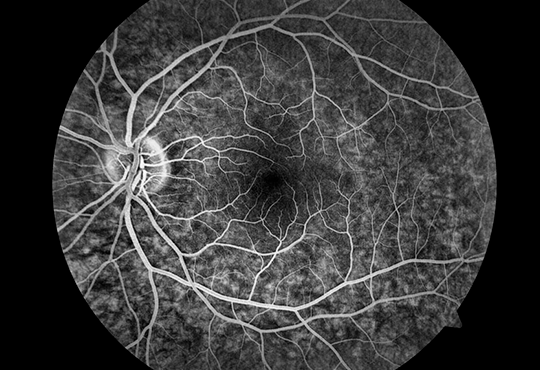

É um exame de diagnóstico que permite visualizar melhor o interior dos vasos sanguíneos, com a intenção de diagnosticar possíveis doenças como aneurisma ou arteriosclerose. A Angiografia ajuda no diagnóstico da Retinopatia diabética, Degeneração macular, Tumores nos olhos e Presença de coágulos.

Geralmente, este procedimento só é feito quando outros exames menos invasivos, como ressonância magnética ou tomografia, não conseguiram identificar corretamente o problema.